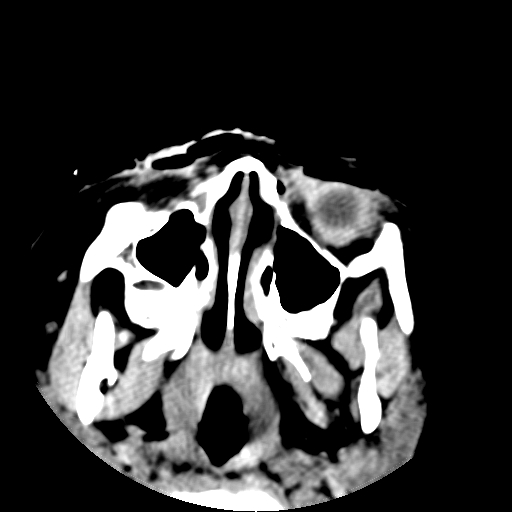

以下是引用深泽交通医院在2009-10-16 8:25:00的发言:[br]右眼环出血伴异物

以下是引用卜一在2009-10-16 15:01:00的发言:[br]右眼球挫裂伤伴异物!

以下是引用拾荒者在2009-10-17 18:38:00的发言:[br]鼻面部皮下积气,右侧睑缘及眼球壁高密度异物影,左侧眼球壁晶状体内侧缘处是圆形低密度影。低密度异物?应提请眼科医生注意。